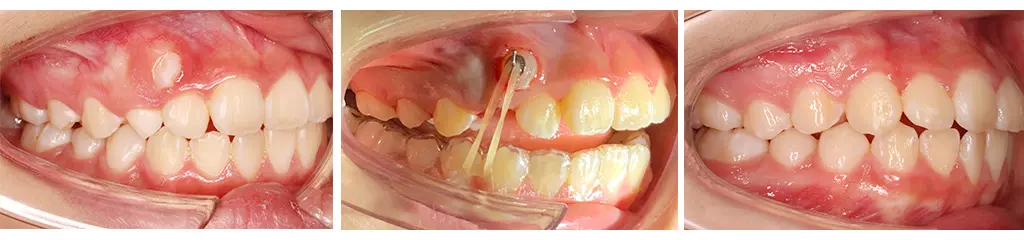

病人小美是國小六年級生,她的乳牙全部都掉完了,唯獨剩下一顆右上乳犬齒。家長原本不以為意,想讓牙齒順其自然生長就好,誰知等了好久好久,這最後一顆乳牙絲毫沒有動搖,不像是會脫落的樣子。更糟糕的是,有一天小美刷牙的時候,發現牙齦上冒出來一坨白白的東西,好像是恆牙長歪了!家長趕緊帶小美來看牙醫。

經過檢查後發現,原來小美的犬齒完全沒有長在應有的位子上,反而從旁邊另闢蹊徑冒出頭來,於是在醫生的安排下進行牙齒矯正治療。首先,要將該掉而未掉的乳牙拔除。由於乳牙的空間不夠容納恆牙,接下來要將空間撐寬,準備好恆牙的位子。最後,在歪掉的犬齒上黏著一個勾勾,請小美每天自己換橡皮筋,把牙齒拉下來。